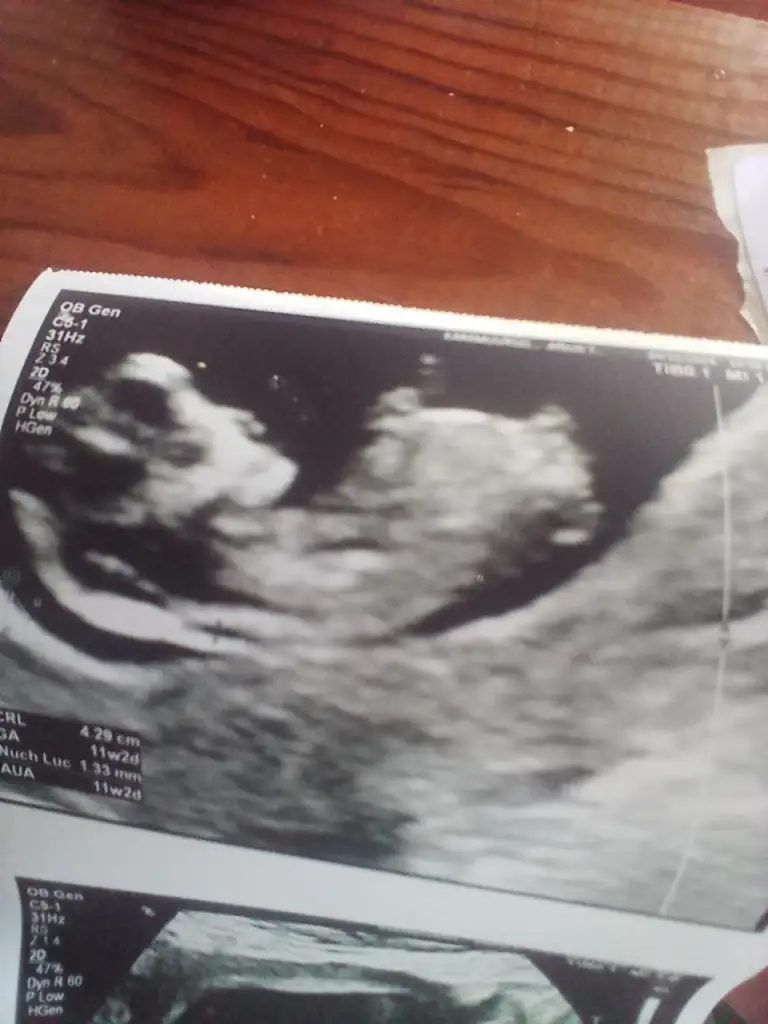

Bu da benimki teyzesi, sen bir tahminde bulunur musunMerhaba benimkini de tahmin edebilir misiniz acaba :)

Benim minnoşa da bak teyzesiErkek oldu kız

Maşallah lokumaTahmin eder misiniz benimkinide

Gerçekten mi insallah gönlümüzden geçen erkek nasip bakalımMaşallah lokumaiçimden erkek geçti çünkü aynı benim oğlumun ultrason görüntülerine bakıyor gibi hissettim. Çok benziyor, arkadan olan görüntüsü hele ki